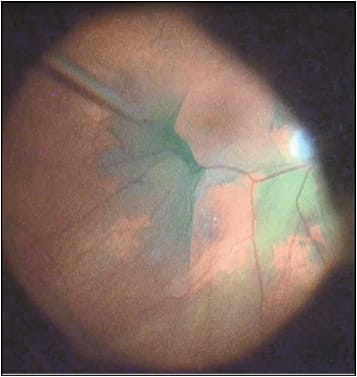

Figure 1. Intraoperative ICG stains the ILM a noticeable green color that helps differentiate it from the underlying retina.